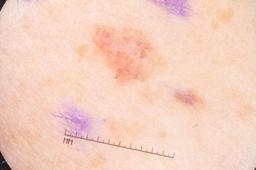

ISIC-DICM-17K (ISIC Dermoscopic Images and Clinical Metadata 17K) is a curated and balanced dataset derived from the International Skin Imaging Collaboration (ISIC) Archive Gallery. It comprises 17,060 dermoscopic images and clinical metadata (8,530 melanoma and 8,530 non-melanoma classes).

For more details, please follow the project’s GitHub repository: https://github.com/mmu-dermatology-research/isic-dicm-17k

This dataset was used in this study and benchmark to explore the effectiveness of multimodal learning for skin lesion classification:

S. Ahammed, X. Cui, W. Lu and M. H. Yap, "Skin Lesion Classification using Dermoscopic Images and Clinical Metadata: Insights from Multimodal Models," 2025 IEEE/CVF Conference on Computer Vision and Pattern Recognition Workshops (CVPRW), Nashville, TN, USA, 2025, pp. 222-230, DOI: 10.1109/CVPRW67362.2025.00027